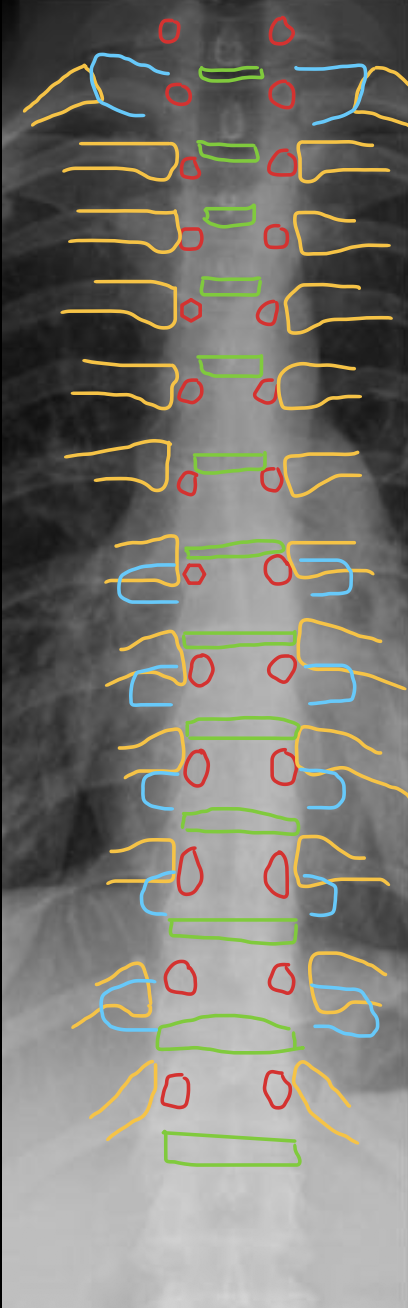

颈椎

CERVICAL

胸椎

THORACIC

腰椎

LUMBAR

椎弓根

Pedicle

T1

椎间盘

Intervertebral disc

关节突关节(小关节)

Zygapophyseal

T2

T3

T4

T5

T6

T7

T8

T9